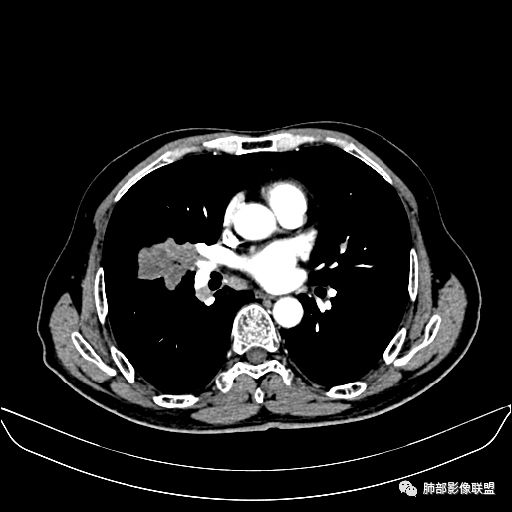

住院4天后行胸部增强CT

动脉期

老年男性,因“咳嗽咳痰1月余。”入院。病程中咳嗽咳痰,咳黄白痰,间断咯少许鲜红色痰血。PPD阳性。胸CT:右肺中叶外侧段支气管管腔阻塞,大片实性病变,病灶边缘光滑,部分边缘膨隆,可见分叶,肺门及纵隔可见肿大淋巴结,并可见钙化。增强可见病灶明显强化,而且延迟强化明显,病灶内多发低密度区,内见血管影,血管变细、部分血管破坏。考虑恶性病变可能性大,鉴别慢性肉芽肿性病变。

胸CT:跨叶大肿块,主体在中叶,右中叶外侧段支气管阻塞,病灶部分边缘膨隆,可见分叶,部分边缘平直,肺门及纵隔可见肿大淋巴结。增强病灶不均匀强化,延迟强化明显,病灶内多发低密度区,内见血管飘浮,部分血管变细、模糊。考虑:恶性病变可能性大,大细胞?淋巴瘤?鉴别慢性肉芽肿性病变。

右肺中叶软组织肿块,外围向内生长,叶间胸膜向前内移位,肿块近肺门侧跨叶,中叶外侧段支气管截断,密度不均匀,双侧肺门及隆突下见肿大淋巴结,增强后呈中度不均质强化,肺动脉供血,多发坏死区,边界尚清,坏死区域内见结构,结合病史考虑恶性,鉴别诊断1结核,爬行征是沿支气管树分布,外宽,内窄,周围有卫星灶,内气管狭窄后扩张,此例沿叶间胸膜长轴分布,气管有截断,不典型。2炎性肉芽肿,符合的地方下方层面增强后延迟性轻度环形强化,不符临床无发热等急性感染病史,实验室指标不符,病灶周围渗出及慢性炎性改变有,不明显。